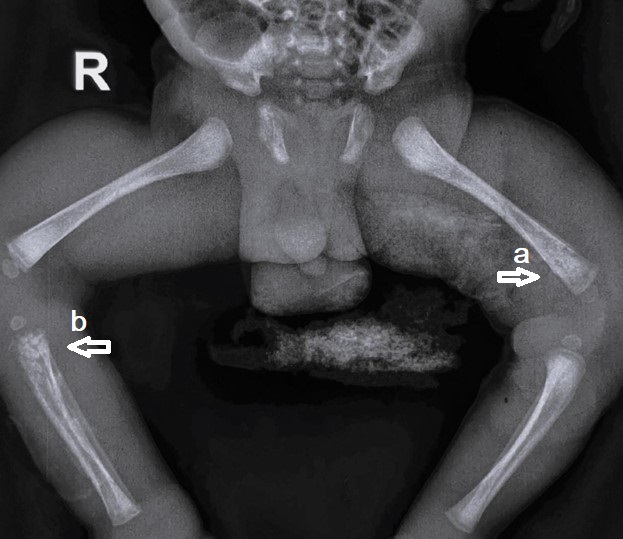

Figure 3

(a) Extensive diaphyseal osteomyelitis in the upper end of the right tibia and (b) Rarefaction distal end of the left femur.

A 15-day-old male baby was admitted with swelling around the right shoulder joint, right knee, and right index finger for 3 days and associated fever for 2 days. There was no history of decreased movements at the shoulder and knee joints. The baby had term gestation and had respiratory distress at birth, kept in the NICU for 5 days on oxygen support—no h/o umbilical catheterization. On examination, the baby had tender swelling with fluctuation around the right shoulder joint. Blood investigations revealed TLC-27,000/uL (N-70%) and CRP-169 mg/L. X-rays of the right shoulder, right knee, and right index finger were normal. Incision and drainage of shoulder abscess was done. Blood culture and Pus culture both had MRSA growth. Inj. Vancomycin was given for 1 week and the baby was discharged on oral linezolid. But the child again got admitted 5 days after discharge, with swelling above the left knee. X-rays were repeated which revealed left distal femur osteomyelitis and right upper tibia extensive diaphyseal osteomyelitis (Fig. 3). Repeat TLC- 22,000/uL (N-56%) and CRP-70 mg/L. Surgical debridement was done. The baby received 4 weeks of i.v vancomycin and was discharged on an oral antibiotic (Linezolid).